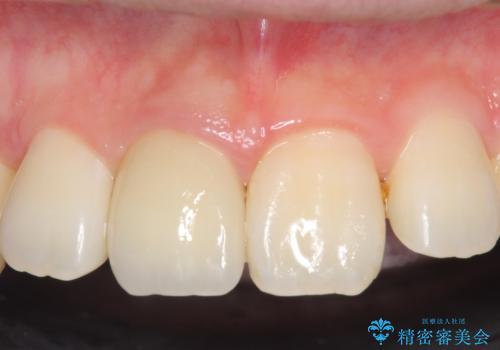

- 右上1番目の前歯の変色が気になるといらっしゃった方の症例です。

再根管治療後、オールセラミッククラウンによる補綴を行いました。

今回用いたオールセラミッククラウンはジルコニアフレームという白い素材の上にセラミックを盛っているため、審美性が非常に高いのが特徴です。

また、ジルコニアは人工ダイヤモンドの材料にも使われているほど高い強度を持っており、そのためオールセラミッククラウンは審美性だけでなく、奥歯やブリッジの補綴も可能とするクラウンです。